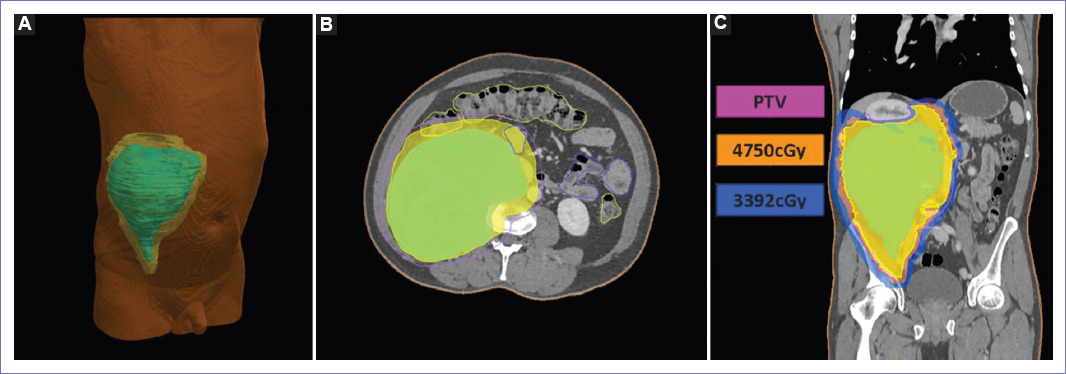

La dosis recomendada es de 50 a 56 Gy en fracciones de 2 Gy. Janssen et al. publicaron un metaanálisis, concluyendo que la radioterapia adyuvante debe considerarse especialmente en aquellos pacientes con resecciones R1 o R2, ya que tienen mayor riesgo de recurrencia18. Se recomienda que el volumen clínico objetivo (CTV) deber ser una expansión de 1 a 4 cm del volumen tumoral macroscópico (GTV) si fuera posible, según la anatomía limitante como intestino delgado; y el volumen tumoral de planificación (PTV) se recomienda una expansión de 3 a 10 mm del CTV, según los accesorios de inmovilización5,19.

En nuestro caso se había optado por realizar una resección parcial del tumor, dejando una mínima enfermedad adherida al cuerpo vertebral, seguido de adyuvancia con irradiación a dosis de 5,600 cGy en 28 sesiones al lecho quirúrgico en técnica especial de arco volumétrico de intensidad modulada (VMAT). Y si el paciente rechazaba la opción quirúrgica inicial, se hubiera abierto la posibilidad de irradiación en técnica especial VMAT con un PTV de 3,728 ml, a dosis de 5,000 cGy, consiguiendo valores de dosis de irradiación a órganos de riesgos, dentro de los parámetros permitidos en la mayoría, a excepción del riñón ipsilateral que se encuentra confinado por la tumoración (Fig. 5). Sin embargo, el paciente no regresó al establecimiento, por lo que se perdió la posibilidad de manejo activo, por el compromiso de la vena cava inferior, empeorando la limitación funcional, solo quedándole la opción de manejo de dolor.

Figura 5 Tratamiento de irradiación. A: reconstrucción tridimensional, localizándose el volumen tumoral macroscópico (GTV) (de color verde) y el volumen clínico objetivo (CTV) (de color amarillo), en hemiabdomen derecho. B: delimitación de los volúmenes de tratamiento, GTV (tumoración grosera, de color verde), CTV (expansión de 10 mm del GTV, de color amarillo) y PTV (expansión de 3 mm del CTV, de color fucsia). C: planificación de irradiación en técnica especial VMAT, con un volumen de CTV y PTV de 3,261 ml y 3,728 ml, con dosis máxima en intestino delgado, y médula espinal de 49 y 44 Gy, con dosis media en hígado, riñón izquierdo y derecho de 20, 12 y 22 Gy.